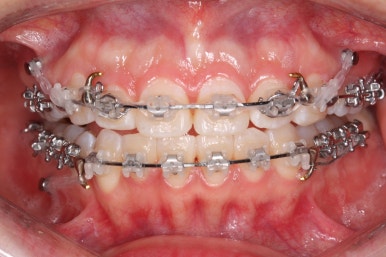

윗니는 발치를 했고, 잇몸뼈에 미니스크류를 식립하여 앞니를 뒤로 당겨넣고 있습니다.

아랫니는 아직 덜 가지런해졌네요.

이 뽑은 자리가 점점 줄어드는 것이 보입니다.

아랫니도 많이 가지런해졌네요.

이 뽑은 자리가 반 이상 줄어든 것 같네요. 아랫니는 마무리를 해도 될 정도로 많이 좋아졌습니다.

이 쯤되면 중간평가를 하게 됩니다.

입 모양을 보고 얼마나 더 넣을지, 앞으로는 어떤 방향으로 치료하게 될 지 다시 한 번 점검하는 것이지요.